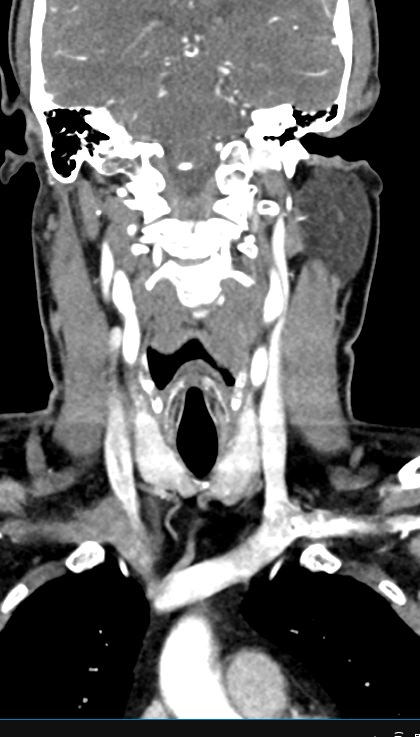

Мультиспиральная КТ сосудов шеи (КТ-ангиография) включает в себя сканирование брахиоцефальных артерий, то есть как сосудов кровоснабжающих головной мозг, так и проксимальные отделы плечевых артерий. Это крупные сосуды, которые отходят от дуги аорты и, разветвляясь, уходят в полость черепа. К ним относятся: брахиоцефальный ствол, общие, наружные и внутренние сонные артерии, подключичные и позвоночные артерии.

КТ сосудов шеи является высокоинформативным методом диагностики патологии брахиоцефальных артерий, который позволяет выявлять участки сужения, патологической извитости, определять развитие атеросклеротических бляшек ещё до того, как появились симптомы заболевания.

В наших медицинских центрах диагностика патологии магистральных сосудов шеи проводится на современных мультиспиральных компьютерных томографах экспертного уровня TOSHIBA AQUILION. Компьютерная томография относится к лучевым методам исследования, то есть для получения изображения внутренних органов используется рентгеновское излучение. Трубка томографа при помощи рентгеновских лучей послойно сканирует область исследования с минимальной толщиной среза от 0,5 мм, затем полученные данные трансформируются в объемные изображения. Оснащение аппаратов позволяет получать снимки и трехмерные реконструкции сосудистой системы превосходного качества, при этом пациент получает минимальную дозу облучения.

Для улучшения визуализации сосудистой системы обязательным является проведение контрастного усиления. Для этого пациенту внутривенно вводится йодсодержащий контрастный препарат, который активно поглощает рентгеновские лучи и обеспечивает яркую видимость даже мелких сосудов на фоне окружающих тканей.